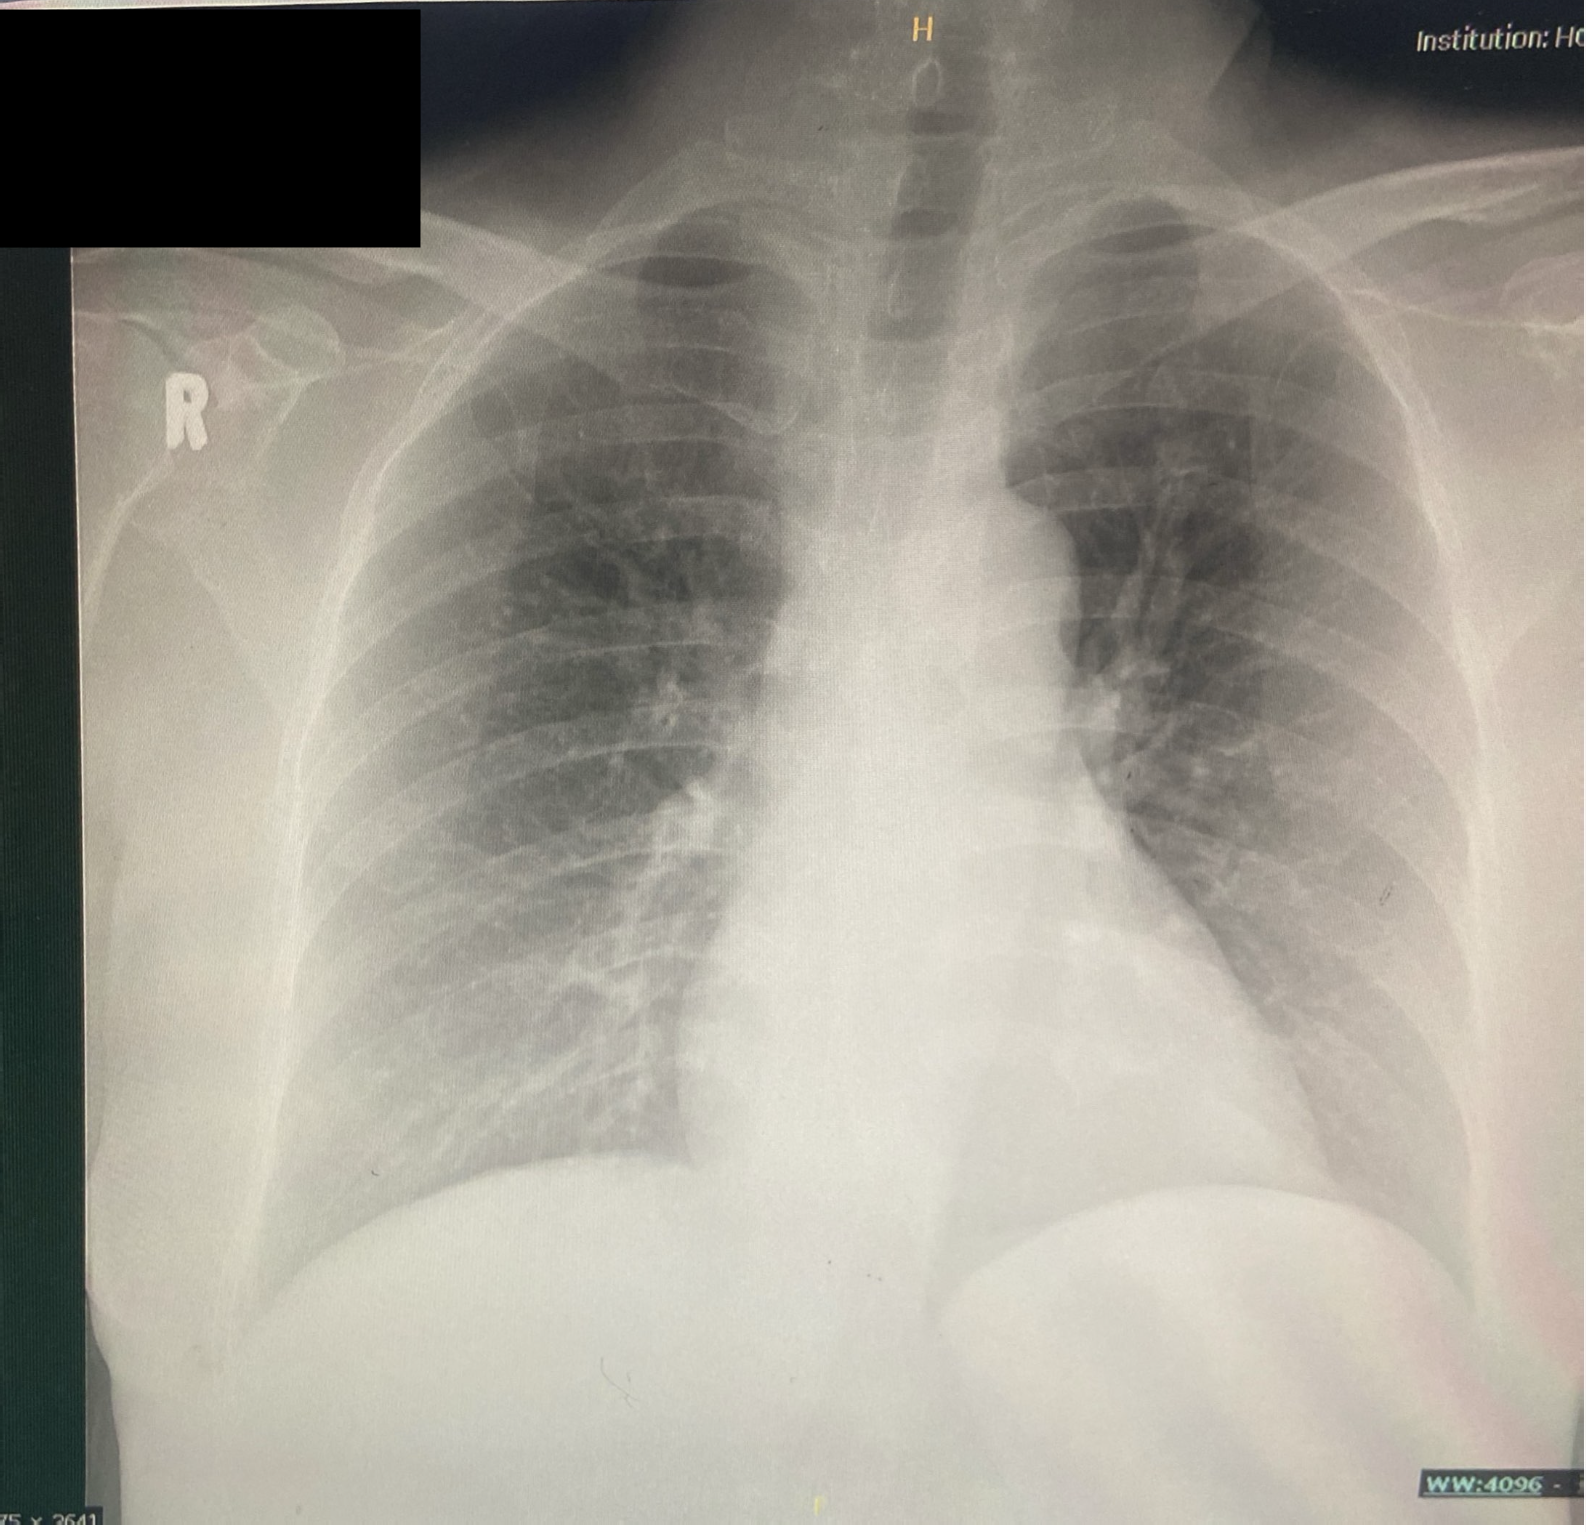

Relevant Test Results Prior to Catheterization

Her initial serum troponin reading was normal, and other blood investigations were unremarkable. The chest x-ray showed no cardiomegaly with clear lung fields. The transthoracic echocardiography revealed hypokinesia involving the base to mid anterior, anteroseptal, and anterolateral walls, extending to the apical anterior wall. The Left Ventricular (LV) Ejection Fraction (EF) was estimated at 41% using Simpson's biplane method, indicating moderately reduced LV systolic function.